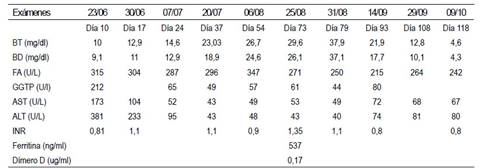

Los exámenes de laboratorio realizados ese mismo día 23 de junio, revelaron cifras anormales de: aspartato aminotransferasa (AST) 173 U/L, alanina aminotransferasa (ALT) 381 U/L, bilirrubina total 10 mg/dl, bilirrubina directa 9,1 mg/dl, fosfatasa alcalina (FA) 315 U/L, gammaglutamiltransferasa (GGTP) 212 U/l e Índice internacional normalizado de tiempo de protrombina (INR) cercano a 1. Se realizaron, además, exámenes serológicos para descartar hepatitis viral A, B, C y E que fueron negativos; marcadores de autoinmunidad como anticuerpo antinucleares (ANA) negativo; anticuerpo antimúsculo liso (ASMA) negativo; anticuerpo antimitocondriales (AMA) negativo; anticuerpo anti liver kidney microsome (LKM-1) negativo; anticuerpo anticitoplasma de neutrófilos con patrón perinuclear (pANCA) negativo; e, Inmunoglobulina (Ig) M: 1,8 g/L , Inmunoglobulina G: 11,8 g/L, Inmunoglobulina A: 0,6 g/L, todas en parámetros normales. La ecografía abdominal demostró ligera hepatomegalia e hiperecogenicidad periportal y la colangioresonancia magnética fue informada como normal.

En el siguiente control ambulatorio efectuado el 30 de junio, día 17 desde el inicio clínico, y con el diagnóstico presuntivo de “injuria hepática inducida por terbinafina”, se efectuaron nuevas pruebas de laboratorio con los siguientes resultados: las transaminasas descendieron casi en un 25%, la FA descendió discretamente, mientras que las bilirrubinas aumentaron asociándose a un prurito intenso, por lo que se indicó antihistamínicos y colestiramina, en el cuarto control ambulatorio la GGTP normalizó y por persistencia de prurito se asoció ácido ursodeoxicólico a dosis de 750 mg al día.

En el sexto control ambulatorio efectuado el 25 de agosto, día 73 desde el inicio clínico, las bilirrubinas totales alcanzaron la cifra de 27,9 mg/dl y el INR se prolongó a 1,35 por lo que se decidió realizar una biopsia hepática por guía ecográfica requiriendo para este procedimiento la hospitalización. Es así que como parte del protocolo de la Institución y hospitalización por la actual pandemia, se solicitaron pruebas para COVID-19 que dieron como resultado: Anticuerpos Ig G positivo y anticuerpos Ig M negativo seguido por una prueba molecular que resultó positiva; sin embargo, el paciente no presentaba ninguna sintomatología asociada a infección por SARS-CoV-2. La radiografía de tórax tenía características normales y los marcadores inflamatorios eran negativos. Ese mismo día se realizó la biopsia hepática, y al día siguiente se procedió al alta hospitalaria para que continúe con sus controles en forma ambulatoria.

El día 31 de agosto, día 79 desde el inicio clínico, las bilirrubinas totales alcanzaron un pico máximo de 37,9 mg/dl, pero con disminución de los niveles de FA, GGTP y transaminasas.

Desde el 14 de septiembre, día 93 de inicio clínico de la enfermedad, las bilirrubinas totales comenzaron a descender progresivamente hasta el día de su último control del 09 de octubre, día 118 de la enfermedad clínica. El prurito casi desapareció por lo que se suspendió la colestiramina y el ácido ursodeoxicolico. Los controles ambulatorios continúan.

La información clínica, de laboratorio (Tabla 1) sobre la evolución del caso que comentamos, corresponde claramente a la de un paciente afectado por una hepatotoxicidad inducida por terbinafina, con un patrón mixto tipo 2<R<5. Se utilizó la Escala CIOMS/ RUCAM para definir la causalidad de la injuria hepática, considerándola probable (8 puntos): comienzo de los síntomas entre 5 y 90 días tras el inicio del tratamiento (+2); evolución analítica favorable, con descenso de la fosfatasa alcalina y bilirrubinas >50% en los 180 días posteriores tras la retirada del fármaco (+2); exclusión de otras causas (+2) y hepatotoxicidad por terbinafina, descrita en el etiquetado (+2).

Tabla 1 Evolución de los exámenes de laboratorio.

ALT: Alanino aminotransferasa; AST: Aspartato aminotransferasa; BT: Bilirrubina total; ; BD: Bilirrubina directa; FA: Fostatasa alcalina; GGTP: gammaglutamiltranspeptidasa; INR: Índice internacional normalizado de tiempo de protrombina